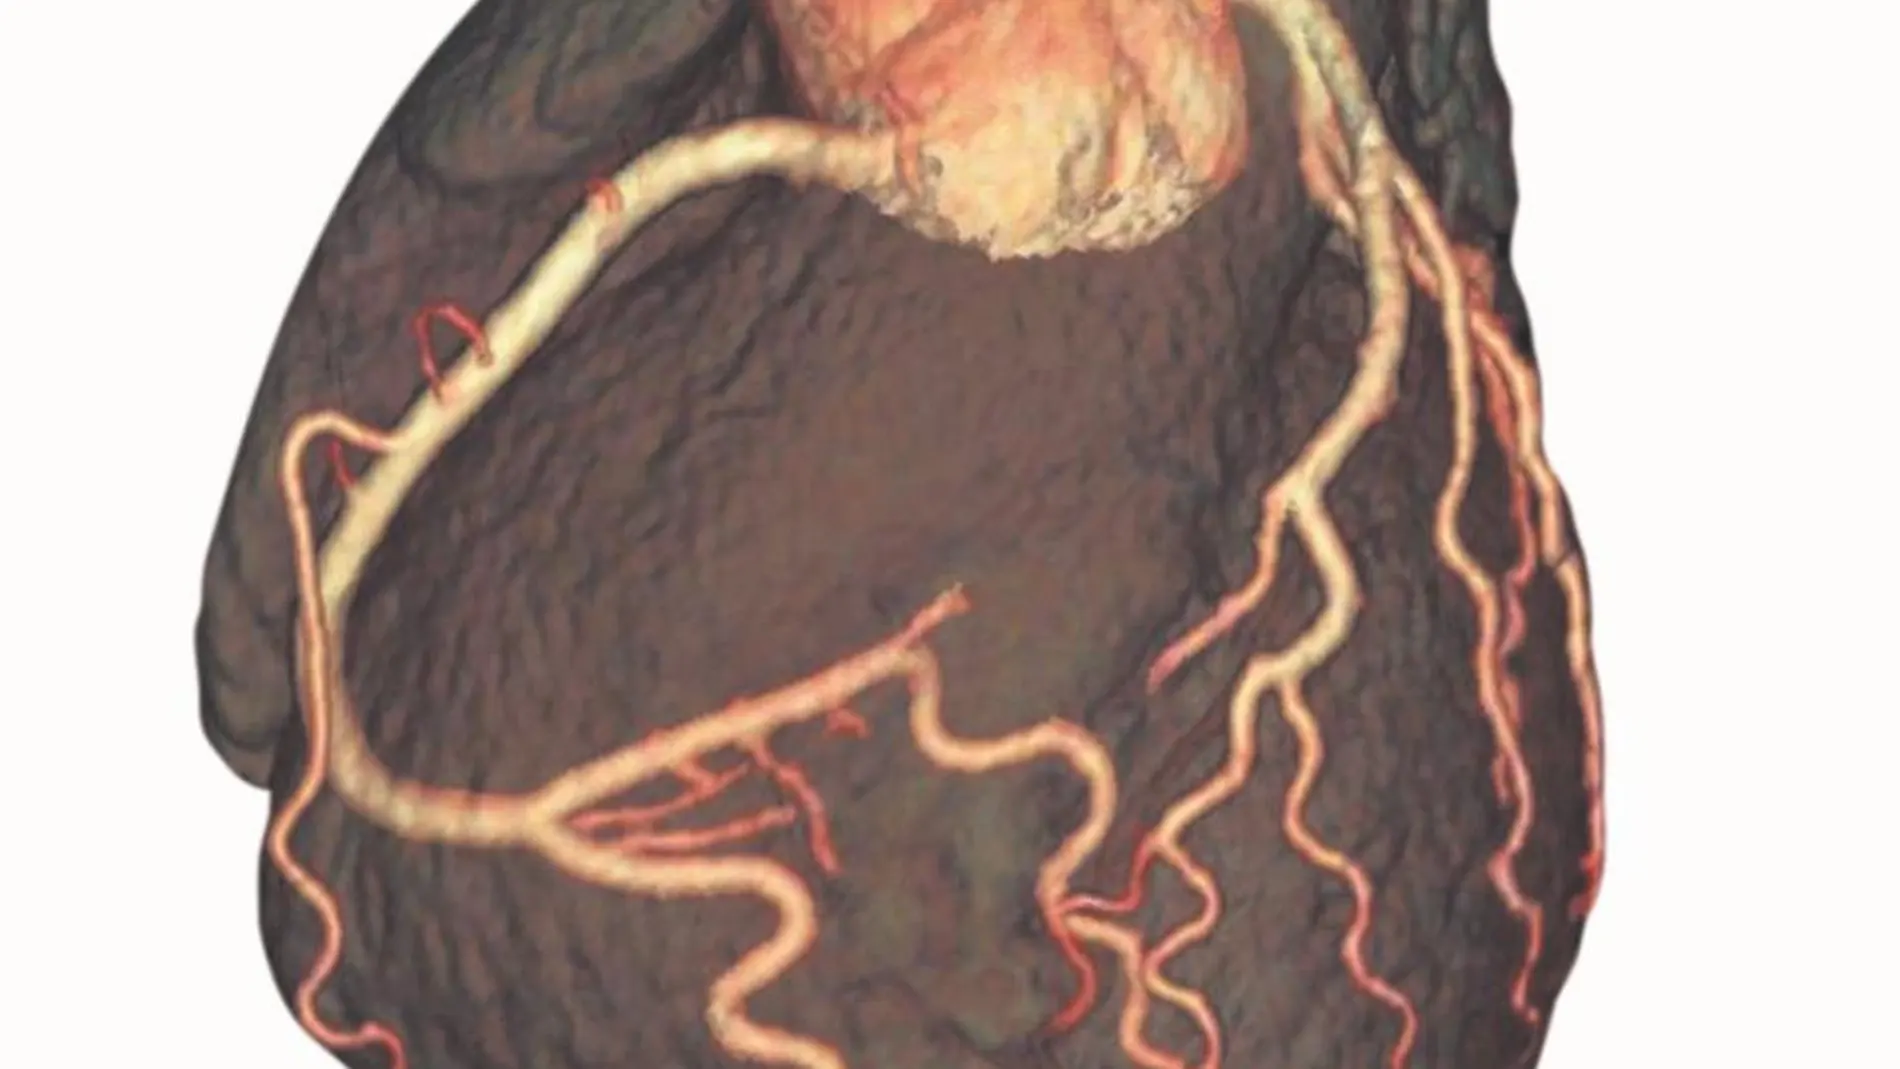

La práctica de ejercicio físico de forma regular, sobre todo en especialidades en las que predomina el componente aeróbico o de resistencia, como la carrera o la bicicleta, produce una serie de adaptaciones beneficiosas para el sistema cardiovascular. «Las principales son el enlentecimiento de la frecuencia cardiaca, un aumento de las cavidades cardiacas, un ligero engrosamiento de los espesores de las paredes del corazón, mejora de la función sistólica y diastólica y mejora de la vascularización, tanto del miocardio como de la musculatura activa periférica», explica el doctor Luis Serratosa, jefe del servicio de Medicina Deportiva del Hospital Universitario Quirónsalud Madrid, y codirector del libro Cardio Deporte. «Todas estas adaptaciones tienen una clara repercusión en la mejora de la capacidad funcional, no sólo para el rendimiento deportivo, sino también para las actividades de la vida diaria. También ayuda a disminuir el riesgo de enfermedad cardiovascular, sobre todo de cardiopatía isquémica». La práctica deportiva, incluso la que se realiza a una intensidad alta y durante muchos años implica numerosos beneficios para el sistema cardiovascular, «tan sólo se ha demostrado un aumento de la incidencia de fibrilación auricular en deportistas que han realizado deporte de resistencia a elevada intensidad durante muchos años, aunque la causa de esta mayor incidencia no está del todo claras».